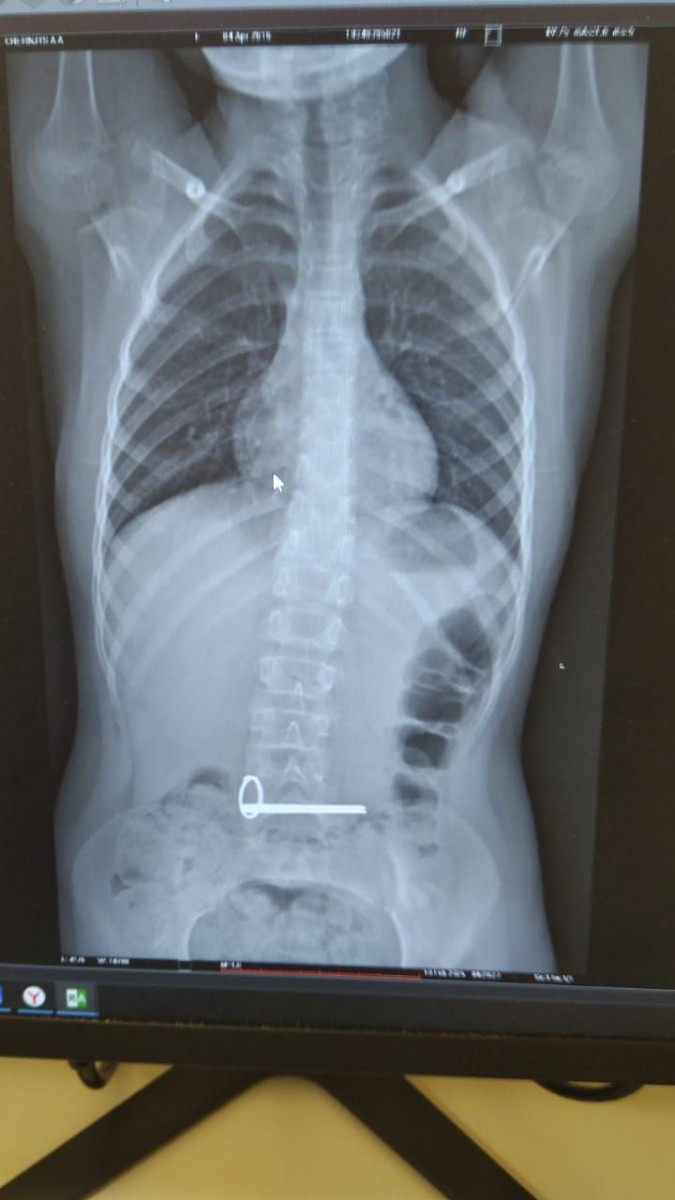

11.02.2025Ночью в отделение экстренной помощи ОДКБ поступил ребёнок с инородным телом в желудке. На снимке, сделанном во время обследования, отчётливо видны два ключа.

Эндоскописты без осложнений извлекли ключи из желудка ребёнка. Операция прошла под наркозом.